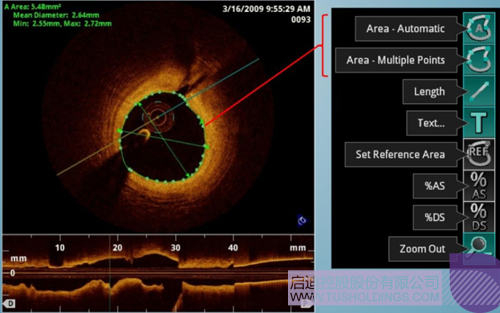

光學(xué)相干斷層成像技術(shù)(OCT)是一種新型影像技術(shù),它利用弱相干光干涉儀的基本原理,檢測(cè)生物組織不同深度層面對(duì)入射弱相干光的背向反射或幾次散射信號(hào),通過(guò)掃描,可得到生物組織二維或三維結(jié)構(gòu)圖像。OCT由于具有極高的分辨率(10 um),可以對(duì)內(nèi)膜性質(zhì)和支架結(jié)構(gòu)更加精確地辨別和分析。

在冠脈介入治療迅猛發(fā)展的今天,隨著復(fù)雜病變患者日益增多,血管內(nèi)影像扮演了越來(lái)越重要的角色。OCT借助其高分辨率的圖像優(yōu)勢(shì),可以提供更清晰的病變特征和支架植入情況,OCT存在以下優(yōu)勢(shì):可更精確的檢測(cè)介入治療后的血管內(nèi)情況,如夾層、支架貼壁不良、組織脫垂等,另外,它在管腔直徑和面積方面的測(cè)量精度更高。

血管腔內(nèi)精準(zhǔn)評(píng)估